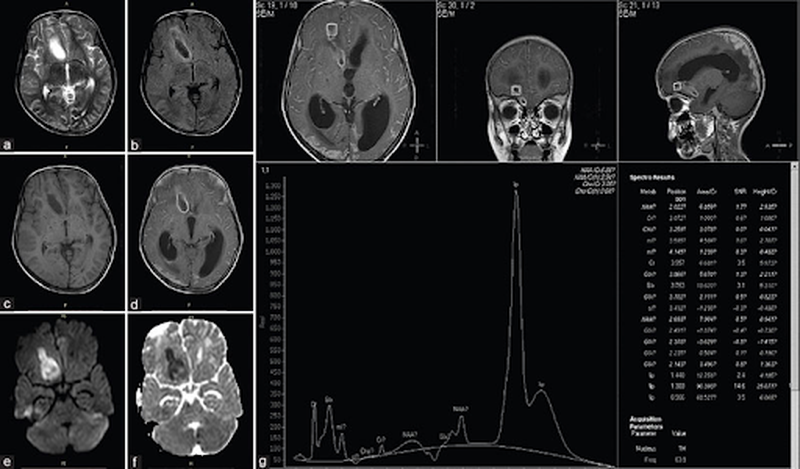

Lao màng não điều trị bao lâu thì khỏi? 3 Hình ảnh chụp CT ở người bị lao màng não